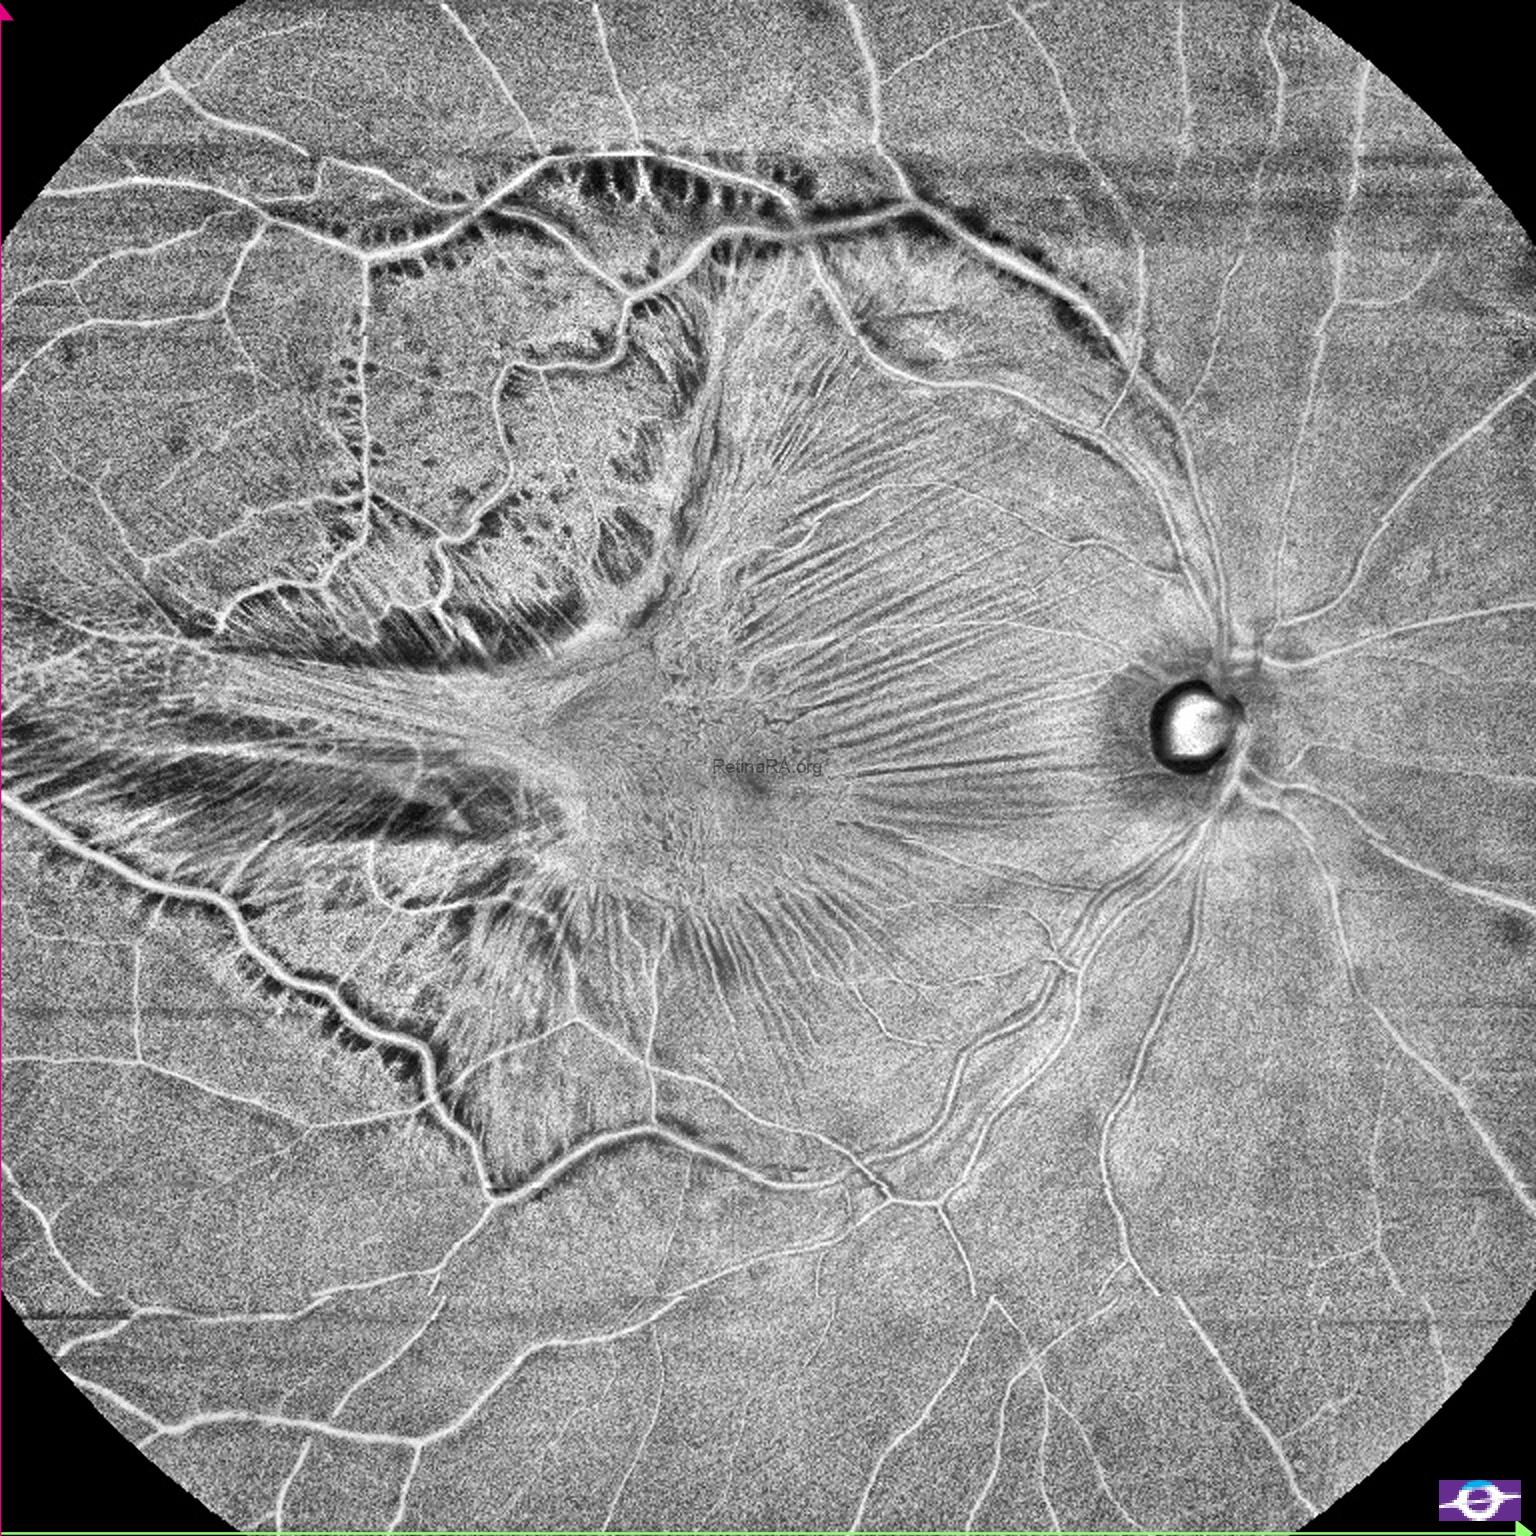

As seen in the color fundus photograph, there was significant tangential macular traction, particularly at the temporal side. Enface OCT demonstrated this remarkably well. It clearly showed the contraction of the epiretinal membrane, distortion of the retina, and traction-related retinal damage.